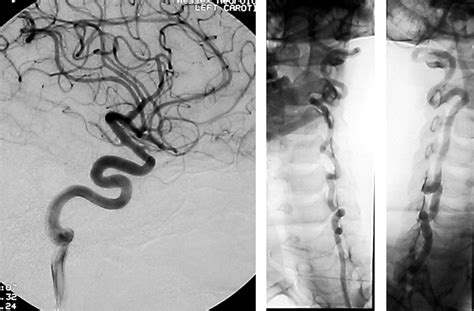

Clinical features in a family with an R460H mut...